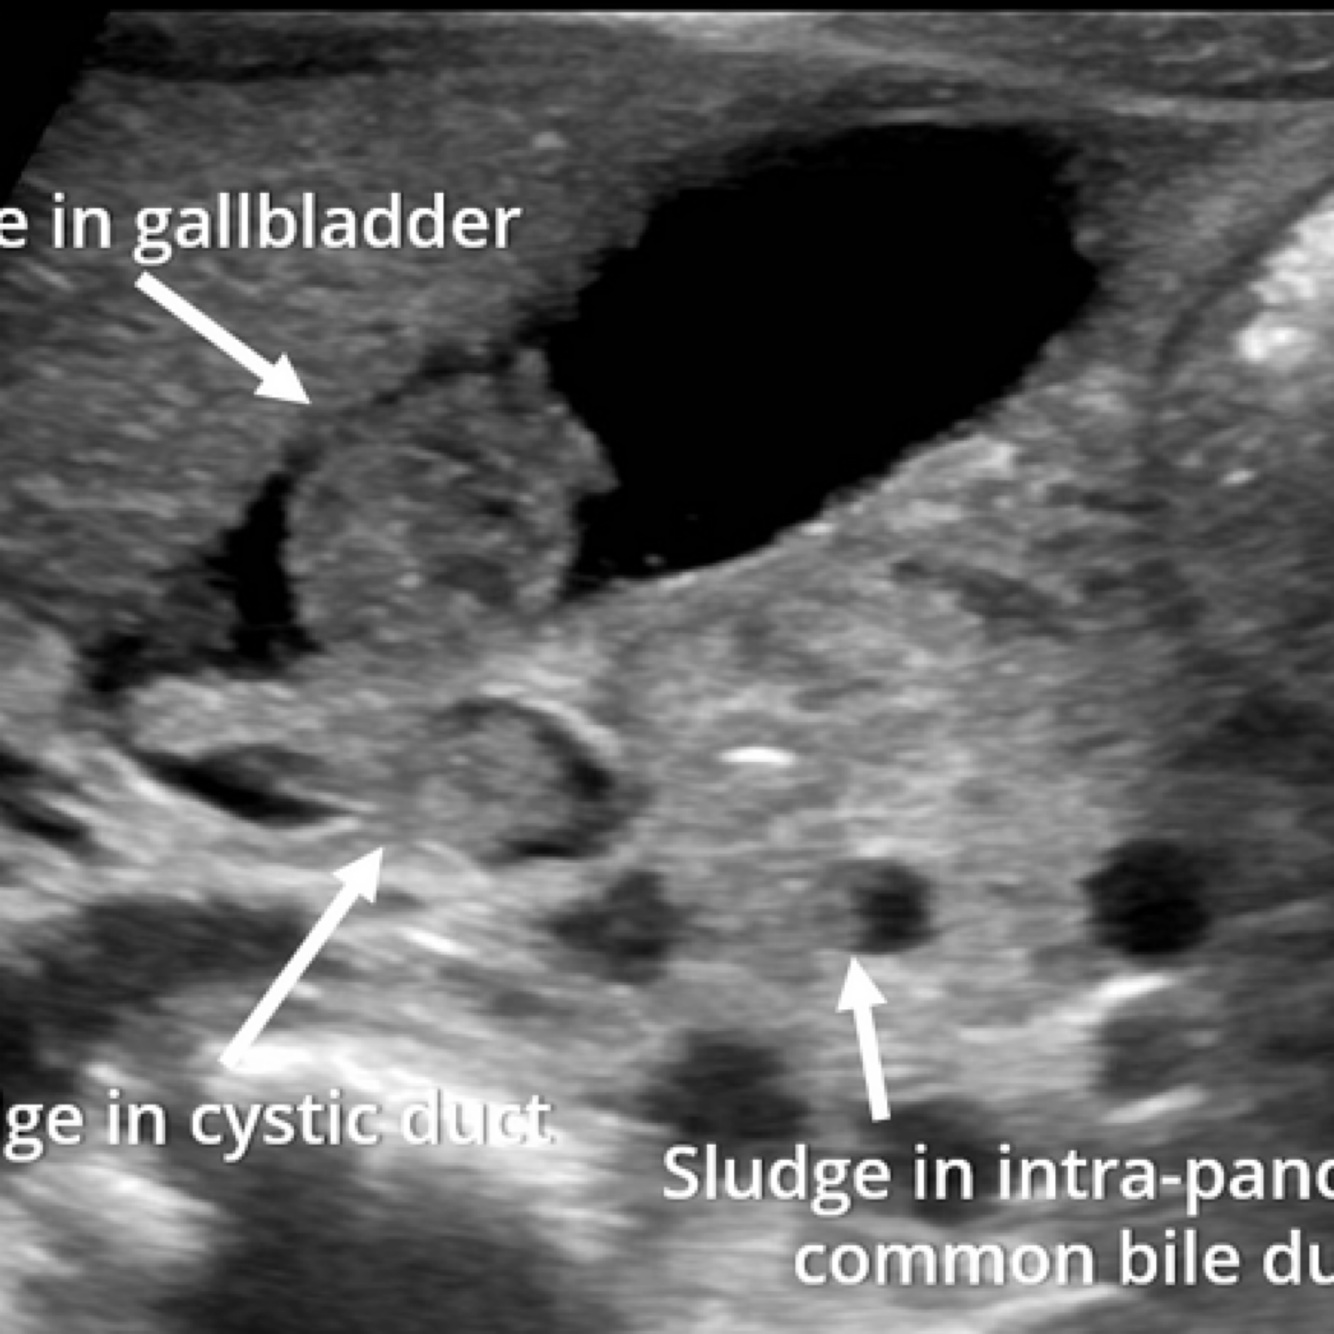

A

Biliary sludge

How well did you know this?

18

Q

GB sludge